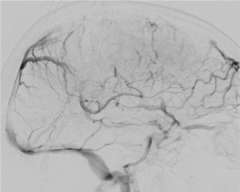

Sinus Thrombosis 3

Figure 3

Anticoagulation, the administration of a blood thinning drug is the first line of treatment and has been shown to be very effective. However, when the clot burden is too large and/or the patient condition deteriorates despite anticoagulation treatment, catheter based clot-busting treatment becomes a consideration (Figure 3).

Using the state-of-the-art interventional suite equipped with the latest biplane X-ray machine, we can safely navigate a catheter into the cerebral venous sinus that is blocked with the clot. Via the catheter, we can deploy a clot-capturing device or aspirate the clot from the catheter itself.